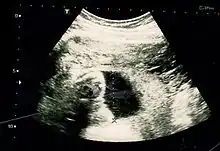

Fetal assessments

Obstetric ultrasonography is routinely used for dating the gestational age of a pregnancy from the size of the fetus, determine the number of fetuses and placentae, evaluate for an ectopic pregnancy and first trimester bleeding, the most accurate dating being in first trimester before the growth of the foetus has been significantly influenced by other factors. Ultrasound is also used for detecting congenital anomalies (or other foetal anomalies) and determining the biophysical profiles (BPP), which are generally easier to detect in the second trimester when the foetal structures are larger and more developed. Specialised ultrasound equipment can also evaluate the blood flow velocity in the umbilical cord, looking to detect a decrease/absence/reversal or diastolic blood flow in the umbilical artery.

X-rays and computerized tomography (CT) are not used, especially in the first trimester, due to the ionizing radiation, which has teratogenic effects on the foetus. No effects of magnetic resonance imaging (MRI) on the foetus have been demonstrated,[4] but this technique is too expensive for routine observation. Instead, obstetric ultrasonography is the imaging method of choice in the first trimester and throughout the pregnancy, because it emits no radiation, is portable, and allows for realtime imaging.

The safety of frequent ultrasound scanning has not been confirmed. Despite this, increasing numbers of women are choosing to have additional scans for no medical purpose, such as gender scans, 3D and 4D scans. A normal gestation would reveal a gestational sac, yolk sac, and fetal pole. The gestational age can be assessed by evaluating the mean gestational sac diameter (MGD) before week 6, and the crown-rump length after week 6. Multiple gestation is evaluated by the number of placentae and amniotic sacs present.

Fetus at 17 weeks

Fetus at 20 weeks